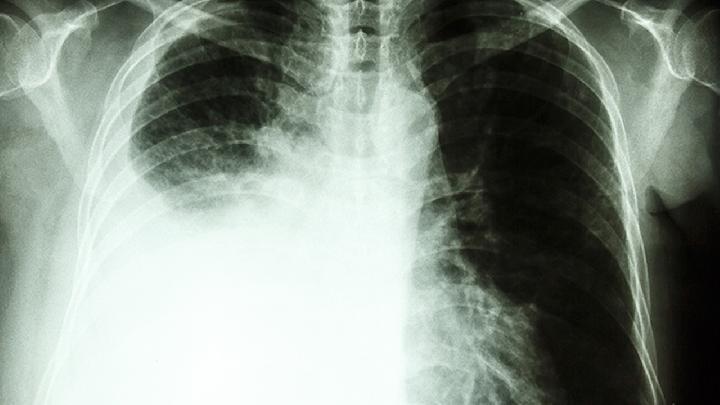

癌胚抗原是一种肿瘤标志物,用于癌症的辅助诊断、病情监测和预后评估。癌胚抗原最早是在结肠癌中发现的一种蛋白质,后来发现在其他类型的癌症中也有一定程度的升高。癌胚抗原检测可以作为辅助手段,帮助医生判断是否可能存在某些癌症,如结肠癌、直肠癌、胃癌、胰腺癌、肺癌、乳腺癌等。对于已确诊为癌症,癌胚抗原水平的监测可以帮助医生评估治疗效果和疾病进展。如果癌胚抗原水平在治疗后持续下降,通常表明治疗有效;如果癌胚抗原水平上升,可能意味着疾病复发或转移。癌胚抗原水平的变化还可以用来预测癌症预后。在某些情况下,癌胚抗原水平较高可能预后较差。癌胚抗原水平升高并不一定意味着癌症,也可能是由其他因素引起的,如吸烟、炎症、某些良性疾病等。癌胚抗原检测通常需要结合其他检查结果和临床表现来综合判断。癌胚抗原水平正常也不能完全排除癌症的可能,因为有些癌胚抗原水平可能始终处于正常范围内。